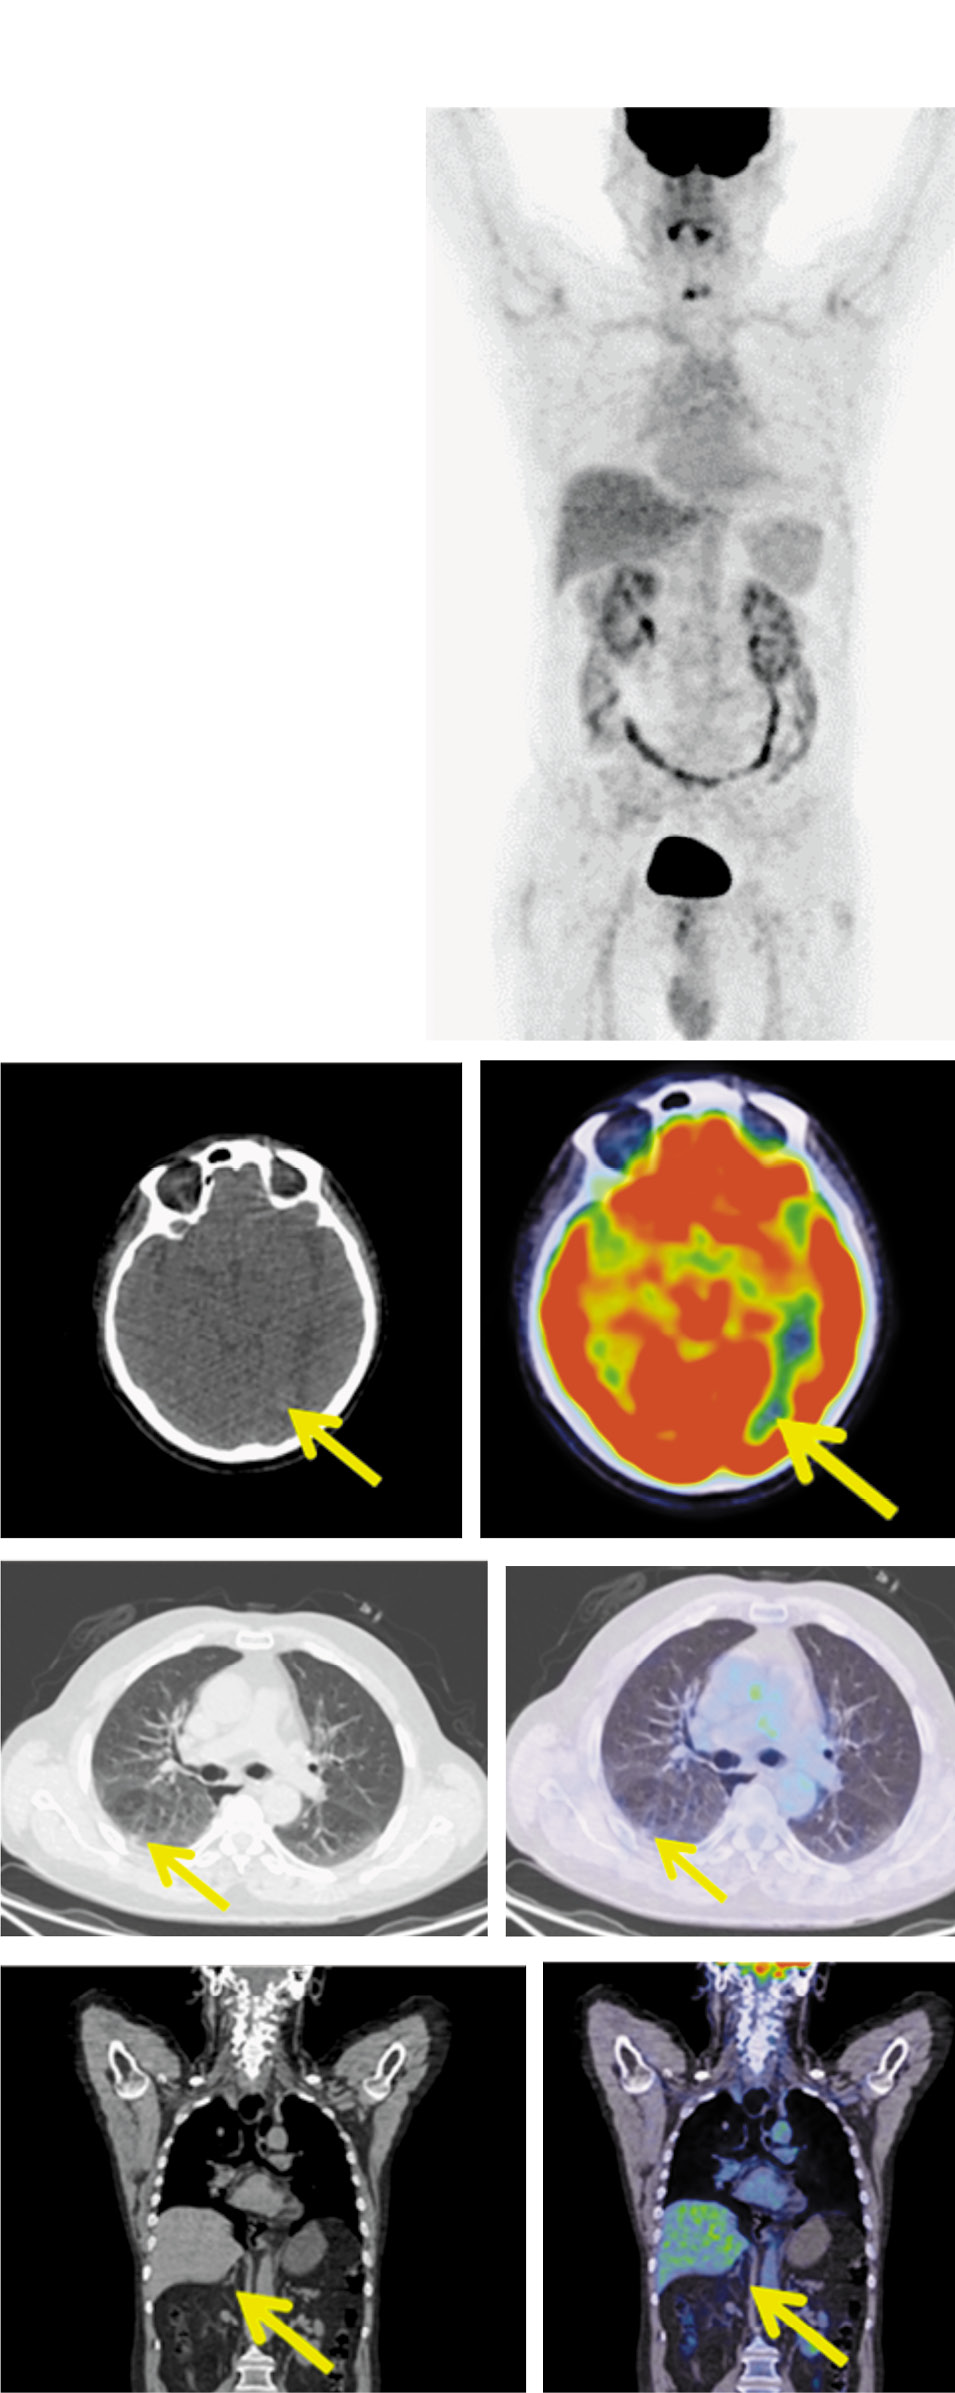

Для оценки эффекта проводимой терапии 26.02.2020, после 14 циклов, выполнена ПЭТ/КТ с 18-ФДГ. В левой затылочной доле очагов фиксации РФП нет. Лимфатические узлы шеи не увеличены, метаболически не активны.

В субплевральном отделе S6 правого легкого сохраняется образование размером до 9 мм без метаболической активности ФДГ.

В задневерхнем средостении паратрахеально справа имеется уплотнение клетчатки без четких контуров, сливающееся с правой стенкой пищевода, размером до 16×13×10 мм без метаболической активности ФДГ, медиастинальные лимфатические узлы не увеличены.

Образование в правом надпочечнике не определяется (рис. 4). По критериям RECIST (Response Evaluation Criteria in Solid Tumors ) v.1.1 получена полная метаболическая регрессия.

Рис. 4. Пациент Н.,64 года. После 14 циклов терапии. На MIP, аксиальной и корональной КТ и ПЭТ/КТ-проекциях в левой затылочной доле очагов фиксации РФП нет. Лимфатические узлы шеи не увеличены, метаболически не активны. В субплевральном отделе S6 правого легкого сохраняется образование размером до 9 мм, без метаболической активности ФДГ. В задневерхнем средостении паратрахеально справа уплотнение клетчатки без четких контуров, размером 16×13×10 мм без метаболической активности. ФДГ, медиастинальные лимфоузлы не увеличены. Образование в правом надпочечнике регрессировало.

Fig. 4. A 64-year-old patient N. The condition of the patient after 12 cycles of therapy. MIP, axial and coronal CT and PET/CT images show the left occipital lobe without increased uptake of radiopharmaceutical. Cervical lymph nodes are not enlarged and without metabolic activity. The lesion measuring 9 mm, without increased RFP uptake is still detected in the subpleural section of the right lung S6 segment. In the posterosuperior mediastinum in the right paratracheal space a fiber compaction with poorly defined boundaries, measuring 16×13×10 mm without RFP uptake is detected, the mediastinal lymph nodes are not enlarged. The lesion on the right adrenal gland has regressed.